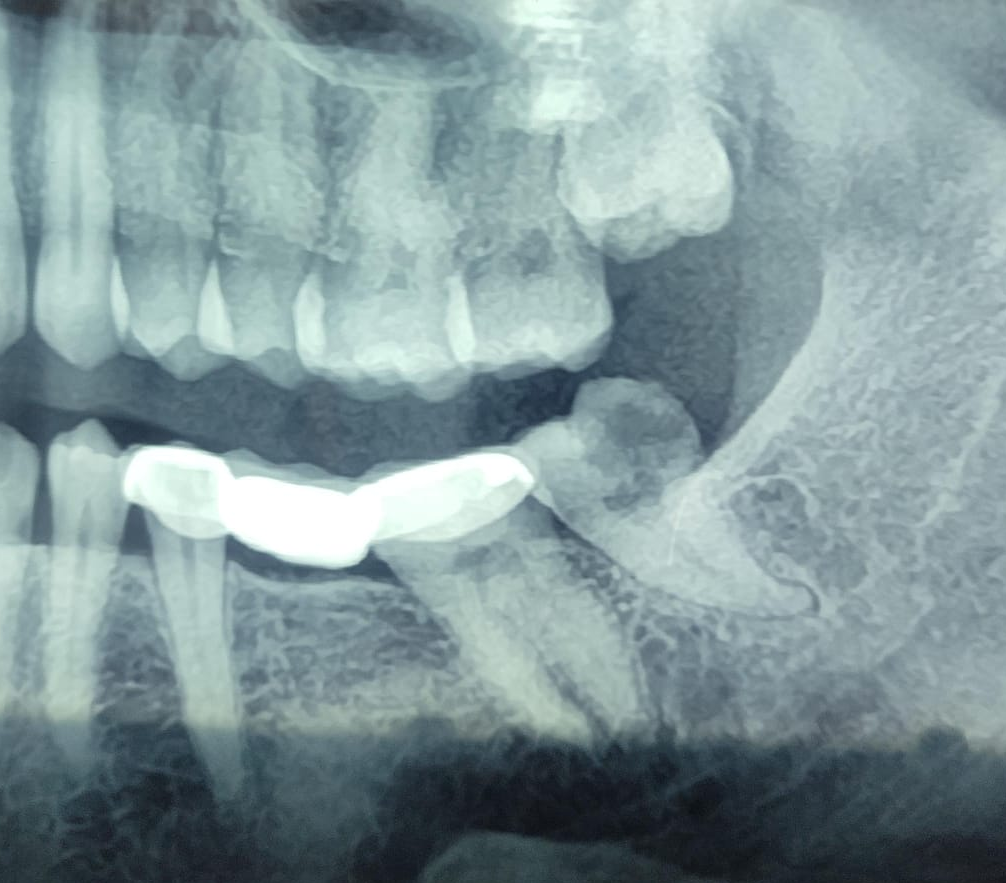

Pre operative lower 38 (3rd molar)(wisdom tooth) OPG view..